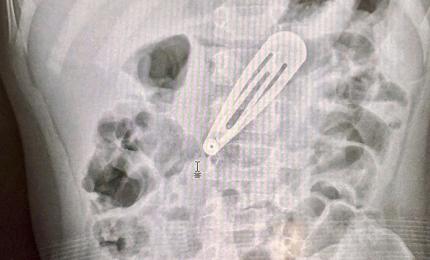

Bé trai 14 tháng tuổi nuốt nhầm hạt nở

Tại Bệnh viện Nhi Trung ương, kết quả chụp X-quang và siêu âm cho thấy bé bị tắc ruột, được mổ cấp cứu.